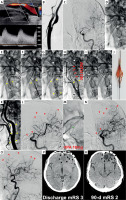

Figure 1

Filter-protected CAS demonstrating limitations of filter protection despite anti-embolic stent use. A 59-year-old man was admitted for carotid revascularisation 2 weeks after left-hemispheric TIA.

Duplex Doppler ultrasound examination showed a fibro-lipidic atherosclerotic plaque in LICA causing a significant stenosis (A). LCCA/LICA angiogram showed a significant LICA stenosis with a visible contrast channel (B). Baseline left cerebral angiogram is shown in C. In absence of Mo.Ma proximal protection on-shelf availability a decision was made to use a distal (filter) cerebral protection and an (routine) anti-embolic stent. The filter was uneventfully delivered through the lesion and was opened in distal LICA (D – white arrowhead). A gentle predilatation was performed with a small coronary balloon (E). There was an acute deterioration of the patient neurologic status with impairment of responsiveness. An anti-embolic stent was implanted (F) and routinely optimised (G). However, “no flow” was visible in the treated artery upon contrast injection (H), consistent with filter blockage by embolic material. Acute neurologic symptoms of left cerebral hemispheric ischaemia were aggravating. To minimise the risk of distal embolism, the filter was removed in a “half-open” position (I). The filter examination showed macroscopic evidence of embolic material (J). Carotid completion angiogram (K) demonstrated an optimal angiographic result at the level of carotid bifurcation. Cerebral angiogram (L) demonstrated multiple distal cerebral artery embolic lesions as well as embolism of the anterior communicating artery (red arrowheads). The latter, however, had a good compensatory filling from the contralateral (right) side; thus, no anterior communicating artery thrombectomy was considered indicated. RtPA (10 mg) was administered to distal LICA via a microcatheter (M), but no symptom improvement (and no cerebral angiogram improvement) occurred over 45 min, consistent with athero-embolic rather than thrombo-embolic mechanism of the multiple distal vessel occlusion. The patient developed a multi-site left hemispheric infarct (N, M – black arrowheads) with clinical symptoms of an acute procedure-related stroke. Discharge mRS (day 9) was 3. On clinical examination at 90-days the patient had residual neurologic deficit but was functionally independent (mRS 2). There were permanent multi-site chronic infarcts on cerebral plain CT (R) that corresponded to the (sub)acute cerebral lesions depicted in P.

Note that filter use in endovascular carotid revascularisation may be associated with distal embolism risk due to (1) unprotected crossing of the lesion, (2) potential filter basket malapposition, (3) embolism by particles < filter pore size, and (4) limited filter basket capacity [5]. On the other han, the anti-embolic stent cerebral protection is exerted only after the stent full deployment and optimisation – but it then extends throughout the stent healing period. These filter limitations do not apply to proximal protection by transient flow cessation or reversal [5, 7, 9, 15]

CT – computed tomography, mRS – modified Rankin scale, LCCA – left common carotid artery, LICA – left internal carotid artery, TIA – transient ischaemic attack.